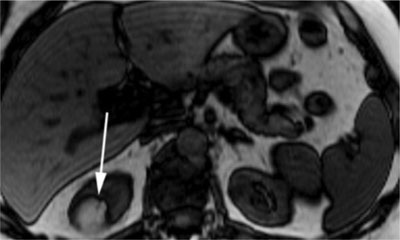

Figure 5

Opposed-phase T1-weighted MR image with a hyperintense renal mass. The India ink artefact (arrow) is present at the interface of the lesion with the kidney [16].